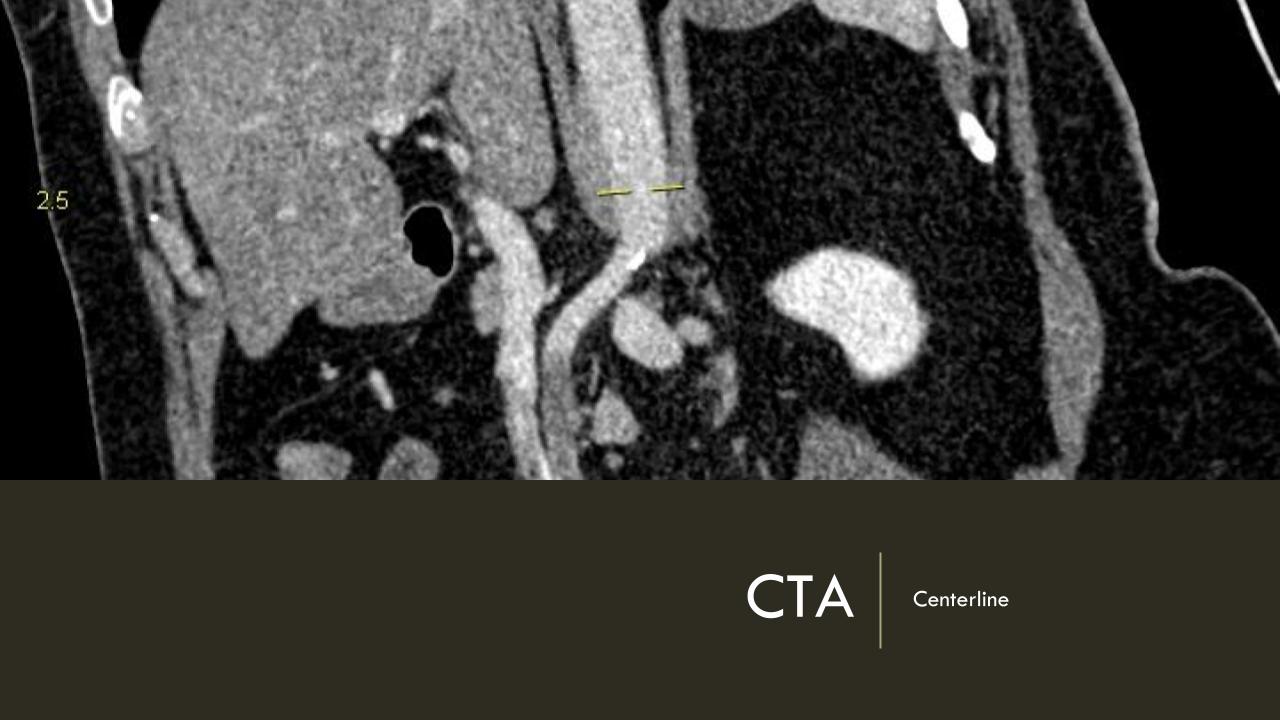

The EVAR was performed percutaneously. No endoleak was detected by completion arteriography (figure). He was soon discharged and was grateful. In followup, CT scan showed excellent coverage of the proximal and distal zones and absence of type III endoleaks. There was increased density to suggest a type II leak, but his inferior mesenteric artery was not the source of it. over a three year period, his aneurysm sac continued its 2-3mm of annual growth despite the presence of the the stent graft.

While CT failed to locate this endoleak, abdominal duplex ultrasound did showing flow from a small surface vessel (duplex below, figure at beginning of post). It was not the inferior mesenteric artery which can be treated endovascularly (link) or laparoscopically (link). CT scan suggested that it was one of those anterior branch vessels that one would encounter in exposing the aorta. Usually these were higher up as accessory phrenic arteries, but these fragile vessels, larger than vasovasorum, but smaller than named aortic branches, are seen feeding the tissues of the retroperitoneum.

Three years of followup showed growth of the AAA sac to 5.5cm, which ironically threshold for repair. Again, no type I or III endoleak could be seen. He reached his calculated repair date, and I discussed our options in detail.